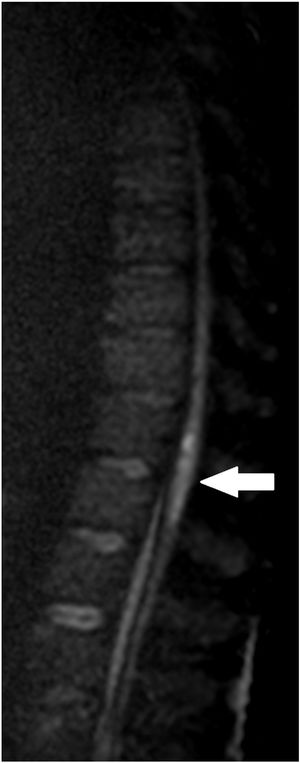

We present the case of a 63-year-old man with liver cirrhosis of mixed aetiology (alcoholic and hepatitis C virus infection) and a diagnosis of a 14-mm hepatocarcinoma in segment III and 40 mm in segment VI. Transarterial chemoembolisation (TACE) of hepatocellular carcinoma was performed by super-selective catheterisation of the feeding arteries of the tumour nodules and they were embolised with doxorubicin (DC-Beads 100−300 μ and 300−500 μ) (Fig. 1). Following the procedure, he developed symptoms consistent with urinary retention, paraesthesia and paresis in both lower limbs with the inability to walk. In the emergency thoracolumbar MRI performed due to suspected spinal cord ischaemia after TACE, an increased signal was observed in the distal portion of the cord and the conus medullaris with moderate restriction in the diffusion sequence (Figs. 2–4), possibly related to an acute ischaemic injury at the level of T11, which was confirmed. Following rehabilitation, the patient was discharged with preserved ambulation.

TACE is based on the almost exclusively arterial vascularisation of the hepatocarcinoma.1 In our patient, the clinical symptoms were accounted for by the existence of an artery feeding the tumour collaterally to one of the spinal arteries that supply the spinal cord, with the chemotherapeutic material entering the spinal cord and inducing unusual transient acute spinal cord ischaemia.